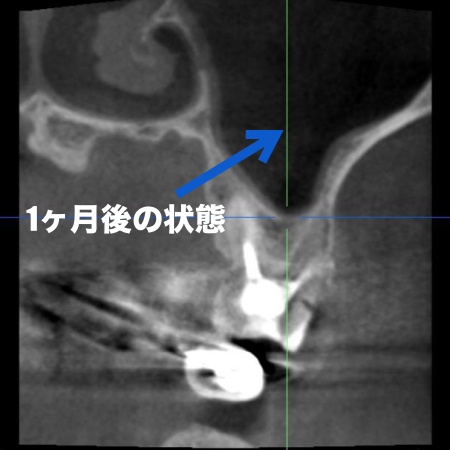

| 診断 | 口腔内を拝見し、レントゲンとCT撮影による詳しい検査を行った結果、左上奥歯の歯根内に細菌感染が起きており、炎症が歯根の先から鼻の横にある空洞「上顎洞(じょうがくどう)」にまで広がっていることがわかりました。

これは、歯性上顎洞炎(しせいじょうがくどうえん)と呼ばれる病気で、鼻づまりや鼻水、膿のにおいがするなどの症状があらわれることがあります。 また、このまま放置すると感染が周囲に広がり、炎症がさらに強くなったり歯を残すことが難しくなったりするリスクが高まります。 以上のことから、細菌に感染した部位を取り除き、歯の温存を目指す治療が必要だと診断しました。 |

治療後